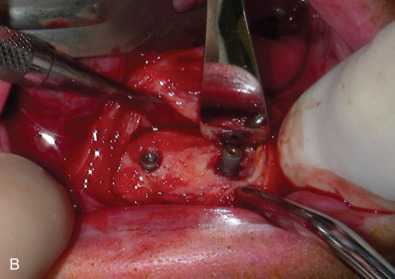

All of these systems allowed for convalescent function – life without MMF. RIF had the potential of dramatically shortening the course of treatment. However, its use was highly technique-sensitive with a steep learning curve. Thus, the incidence of complications increased dramatically due to operator error. Complications related to inadequate reduction – “the OIF” (open internal fixation … without the reduction) ( Figs. 1.16.1–1.16.3 ), inadequate fixation ( Figs. 1.16.4–1.16.7 ) and surgical misadventure ( Fig. 1.16.8 ) began to appear. Indeed, by the early 1990s operator error was the number one cause of mandibular fracture complications. Quite obviously, RIF is very unforgiving. When done poorly, one has a rigidly fixed mistake. The latest series of misadventures are related to the use of IMF screws. Bone-anchored arch bars will most likely be next. Not all believe that RIF and convalescent function is cost-effective with respect to the increased cost, potential for complications, and patient acceptance.